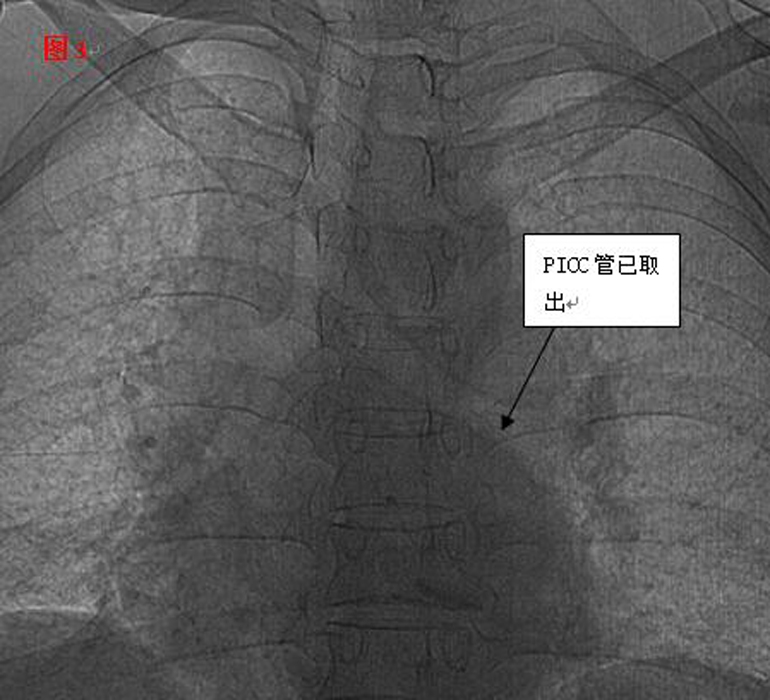

??? 手術(shù)遇到了艱巨的挑戰(zhàn),需更改手術(shù)方案。血管外科專家王李華教授及陸煒主任短暫商討后,臨時(shí)施妙招,先將PICC導(dǎo)管拉出心臟,再將圈套器牽引導(dǎo)管至下腔靜脈,捕捉后緩慢拉出體外,導(dǎo)管竟長(zhǎng)達(dá)30cm(見圖2)。

??? 憑借醫(yī)師的高超技術(shù)加上團(tuán)隊(duì)的密切合作,手術(shù)圓滿成功,30厘米的導(dǎo)管被完整取出,術(shù)后復(fù)查未見殘留。當(dāng)手術(shù)結(jié)束的那一刻,躺在手術(shù)臺(tái)上的麗琴由衷的感謝聲,以及在場(chǎng)觀摩學(xué)習(xí)人員的掌聲,讓手術(shù)室內(nèi)格外溫情。